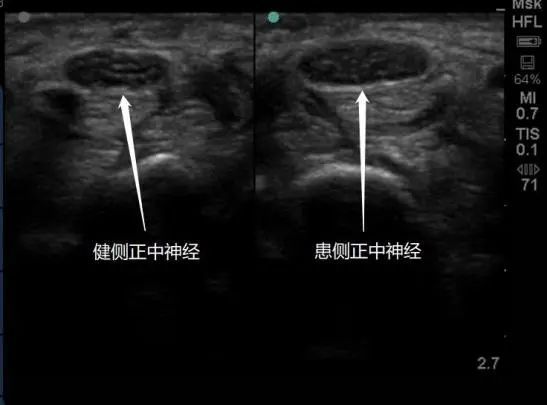

超声影像显示双侧正中神经对比

随着超声影像技术的发展,肌骨超声已成为集诊断、评估、治疗于一身的重要方法。姜丽表示,超声影像引导为神经水分离技术保驾护航,让治疗更精准有效,超声影像可以直接观察到神经的形态变化,有助明确病因、评估受损程度,减少徒手穿刺(盲打)的相关并发症,确保药物精准注射,用药更少、疗效更佳,同时也更安全、精准、有效。姜丽团队关于超声影像引导神经水分离技术治疗腕管综合征研究的相关文章,近期也被收录于Frontiers in Neurology杂志上。